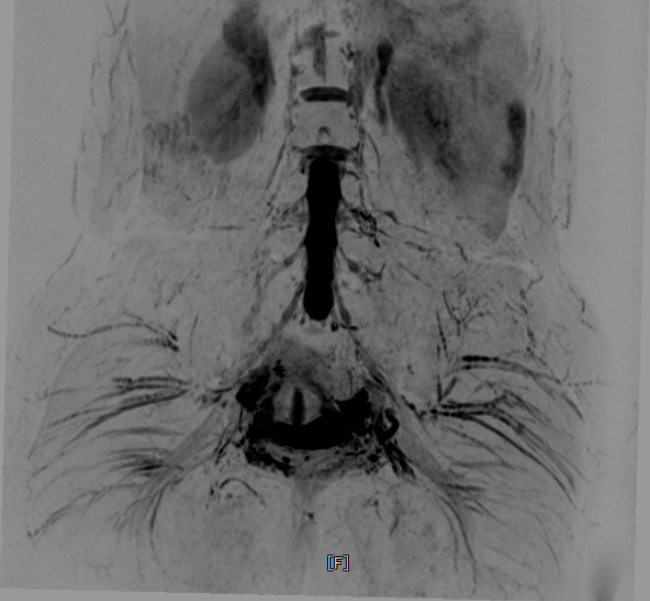

腰丛神经-MIP